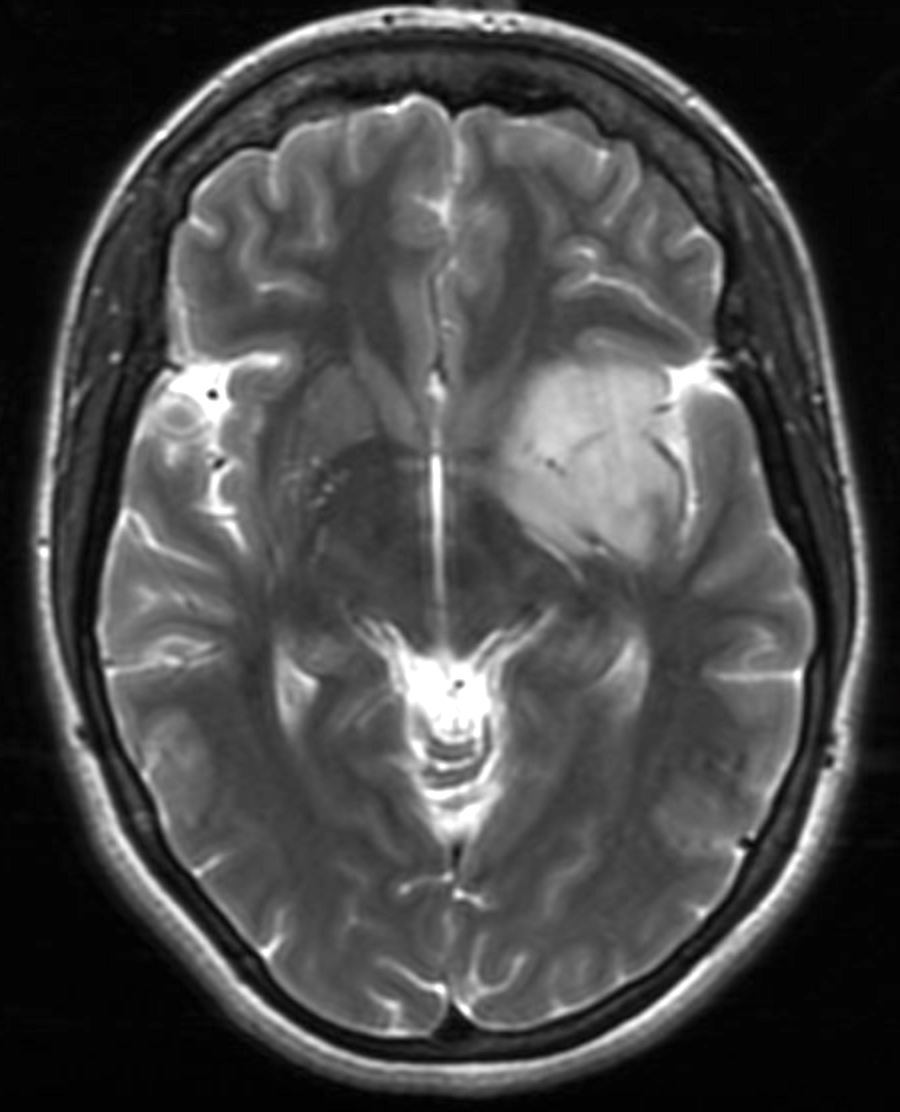

Radiology description

- Computed topography (CT):

- Mixed density (hypodense and isodense) located in cortex or subcortical white matter (Radiology 2017;284:316)

- High attenuation areas, likely from calcifications

- MRI:

- Heterogeneous on T1 and T2 weighted imaging

- Typically no diffusion restriction

- Poorly circumscribed borders (AJNR Am J Neuroradiol 2017;38:678)

- Cystic changes are relatively common (Radiology 2017;284:316)

- Contrast enhancement present in < 20% of WHO grade 2 tumors and > 70% of WHO grade 3 tumors (AJNR Am J Neuroradiol 2012;33:852, Eur J Cancer 2019;107:15)

- Elevated 2HG by magnetic resonance spectroscopy could serve as radiologic surrogate of IDH mutation status (Nat Med 2012;18:624)

Radiology images